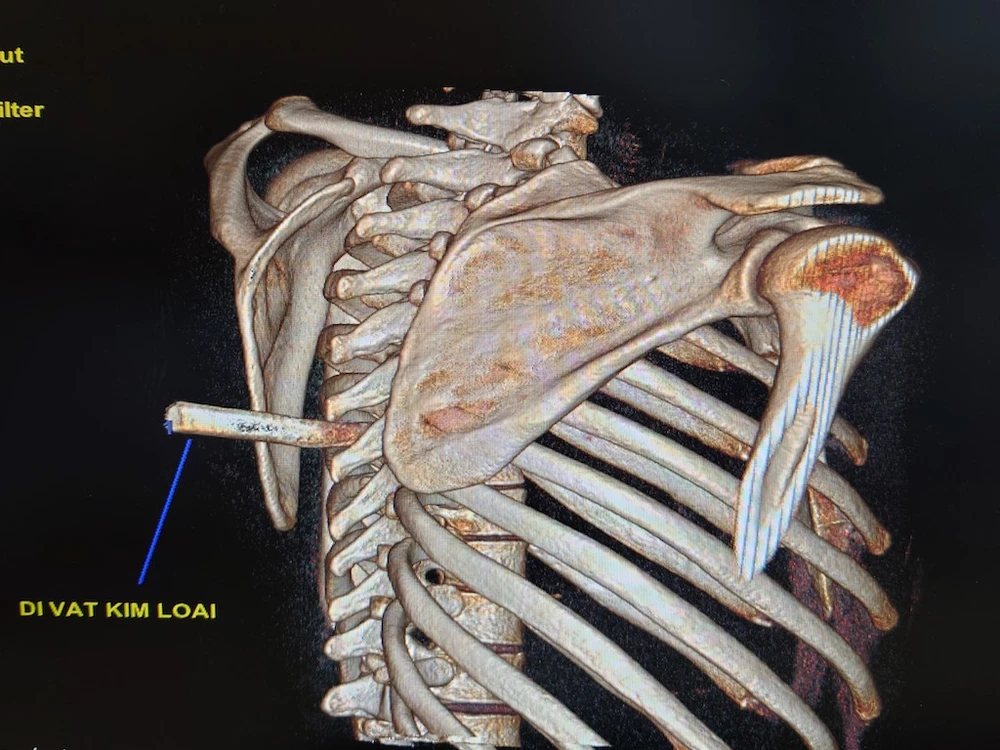

Hình ảnh CT cho thấy mũi dao đang cắm vào đốt sống bệnh nhân. Ảnh: BVCC

Qua hội chẩn, ê kíp phẫu thuật đã tiến hành lọc mỏm gai ngực 6-7, tách cơ cạnh sống bên trái. Hiện trạng dao dài 5x2cm đâm xuyên từ bên trái mỏm gai ngực 5 xuyên xuống vào trong, chạm vào bản sống ngực 7 gây nứt thành ngoài khiến cho mũi dao bị cong.